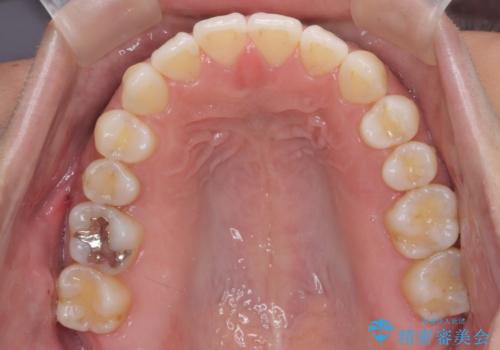

受け口、すきっ歯を インビザラインで モニター治療

- 前歯のすき間と受け口を気にして来院。

マウスピースでしっかり閉じています。

下の前歯を後方に移動するため、ゴムを上下のマウスピースにかけてもらいました。